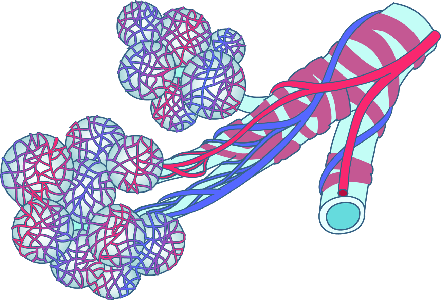

Detailreiche Fotografien aus der medizinischen Praxis ergänzen die Texte; moderne, genaue,

wissenschaftliche Zeichnungen geben Einblick in die Anatomie und die Funktion der Lunge und

anderer Organe.